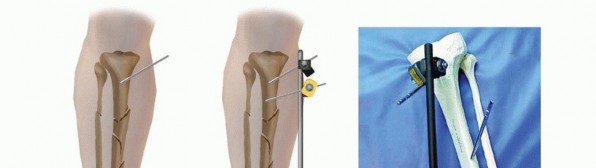

Monolateral Four-Pin Frame Application for Tibial Shaft Fracture Contemporary simple monolateral fixators have clamps that allow independent adjustments at each pin-bar interface, allowing wide variability in pin placement, which helps to avoid areas of soft tissue compromise. Because of this feature, simple four-pin placement may be random on either side of the fracture. ### Option 1 The initial two pins are first inserted as far away from the fracture line as possible in the proximal fracture segment and as distal as possible in the distal fracture segment ( TECH FIG 2A). A solitary connecting rod is attached close to the bone to increase the rigidity of the system. Longitudinal traction is applied and a gross reduction is achieved ( TECH FIG 2B-F). The intermediate pins can then be inserted using the pin fixation clamps attached to the rod to act as templates with drill sleeves as guides. These pins should not encroach on the open wound or severely contused skin in the immediate zone of injury. After placement of these two additional pins, the reduction can be achieved with minimal difficulty by additional manipulation of the fracture. Once satisfactory reduction has been accomplished, the clamps are tightened and reduction is confirmed via fluoroscopy. ### Option 2 Alternatively, all the fixation pins can be inserted independent of each other, with two pins proximally and two pins distally ( TECH FIG 3). The two proximal pins are connected to a solitary bar and the distal two pins are connected to a solitary bar. Both proximal and distal bars are then used as reduction tools to manipulate the fracture into alignment. Once reduction has been achieved, an additional bar-to-bar construct between the two fixed-pin couples is connected. Reduction is confirmed under fluoroscopy. 538

### TECH FIG 2 • Placement of a simple four-pin monolateral fixator. A. Two pins are placed on either side of the fracture as far from the fracture as possible. A connecting bar is then attached to the two pins (B) and a gradual reduction is performed (C-F). Two pins are then placed as close to the fracture as possible on either side, after longitudinal traction has accomplished a reduction. The inner pins are then attached, and the reduction is fine-tuned. 539

### TECH FIG 3 • Alternative method for simple four-pin monolateral fixator. A,B. Once the bar is attached, two intercalary clamps can be positioned as templates for the placement of the interior pins. C. Final construct after interior pin placement. D. The proximal and distal two pins can be attached to each other by a solitary bar. These bars can then be used as tools to reduce the fracture. E. The two bars are then connected by a solitary bar, and the fracture reduction is maintained. F,G. Closed fracture with associated compartment syndrome is reduced and stabilized using a four-pin fixator with a double stack bar for stability, and the foot is spanned to maintain a plantigrade foot. H. Similar tibial fracture reduced with four pins and a single bar. Note pins out of plane to each other to facilitate ease of pin insertion.